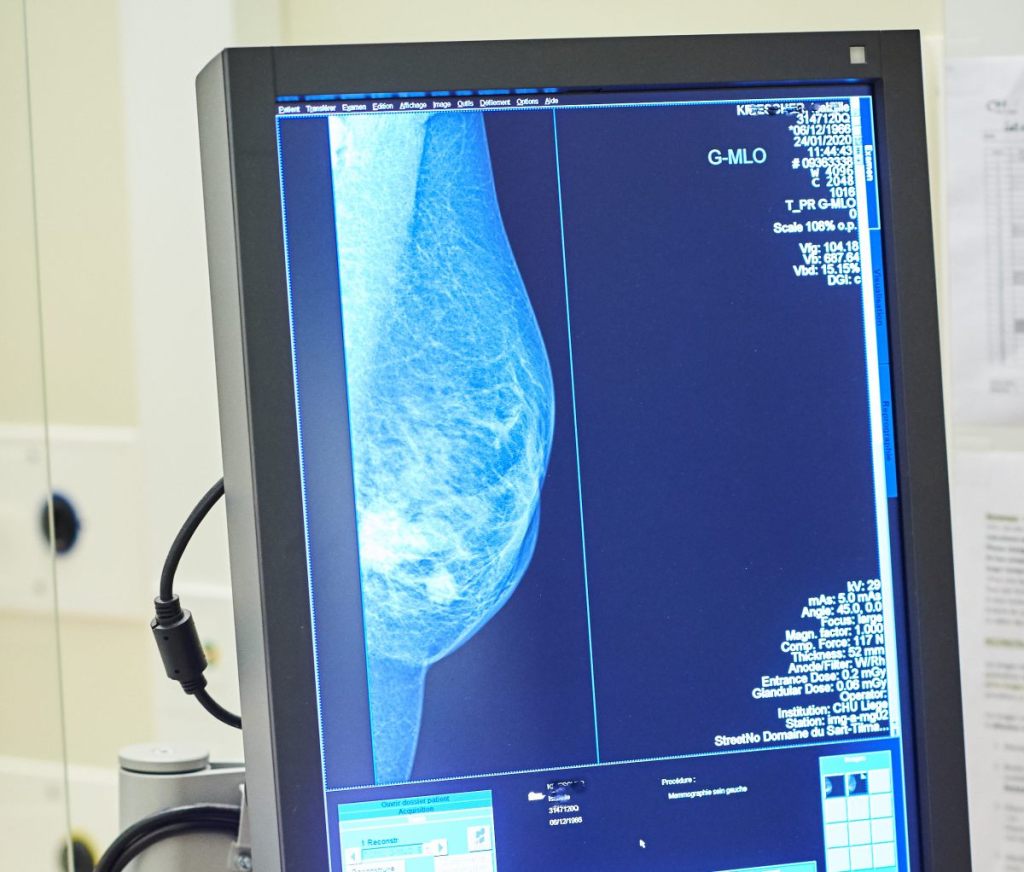

ROMA (ITALPRESS) – A quasi tre mesi dall’istituzione dell’apposito fondo nazionale di 20 milioni di euro, i test genomici per il carcinoma mammario non sono ancora disponibili gratuitamente in tutta Italia. “Per migliorare la qualità di vita delle pazienti e permettere risparmi di preziose risorse pubbliche bisogna accelerare le procedure affinchè questi esami siano disponibili senza alcuna spesa. Per questo chiediamo un intervento diretto e immediato del Ministero della Salute affinchè approvi al più presto il decreto attuativo”. E’ questo l’appello che sostiene Europa Donna Italia, il movimento per la tutela dei diritti delle donne con tumore al seno che a inizio 2021 ha avviato la campagna nazionale “Chemio: Se Posso la Evito”. I principali risultati dell’iniziativa sono stati presentati oggi in una conferenza stampa virtuale. In poco più di due mesi sono state raccolte oltre 15.000 firme ad una petizione on line. Sono poi stati raggiunti oltre 564mila utenti del web attraverso un’intensa attività sui principali social media.

“Abbiamo ottenuto buoni risultati e un ottimo sostegno da parte di pazienti, caregiver, clinici e semplici cittadini – afferma Rosanna D’Antona, presidente di Europa Donna Italia -. Si tratta di una chiara testimonianza che conferma quanto sia sentita la necessità della personalizzazione delle cure, soprattutto in questo momento difficile caratterizzato dal Covid-19. Europa Donna Italia si è battuta perchè non solo in Lombardia, Toscana e Provincia Autonoma di Bolzano – dove i test sono finanziati da fondi regionali – ma in tutta la Penisola si possa evitare la somministrazione di chemioterapie inutili. Sono circa 8.000 le pazienti che, ogni anno, ricevono queste cure anche se non ne hanno necessità. Ringraziamo il Governo e il Parlamento per quanto fatto finora. Bisogna però al più presto emanare il provvedimento che renda effettivamente utilizzabili i test genomici senza costi per le donne”.

“Questi esami rappresentano una fonte di risparmio importante per i conti pubblici – aggiunge il professore Carlo Tondini, direttore Oncologia Medica dell’Ospedale Papa Giovanni XXIII di Bergamo -. Nello studio BONDX, condotto in Regione Lombardia su 400 pazienti, abbiamo provato a quantificare da un punto di vista economico i vantaggi ottenuti. La ricerca ha evidenziato come l’uso di due test, da 2.000 euro ciascuno, abbia evitato una chemioterapia dal costo di 7.000 euro. Il risparmio diretto sulla spesa farmaceutica regionale ammonta a circa 3.000 euro per paziente a cui vanno aggiunti i costi indiretti per malati e caregiver. Abbiamo, inoltre, evitato ad una donna di essere sottoposta ad una chemioterapia, dopo l’intervento chirurgico, e preservato così la sua qualità di vita evitando effetti collaterali”.